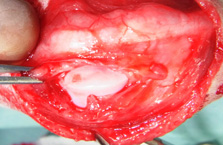

尺骨骨折を伴った肘関節脱臼

手術前レントゲン写真

手術後レントゲン写真

手術中の肘関節の写真